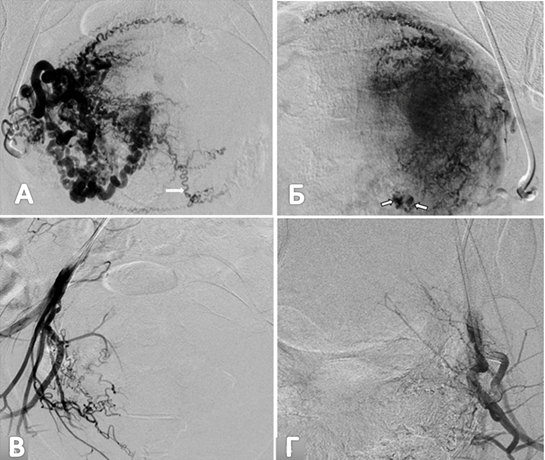

Хирургические процессы при эмболизации гемангиомы на фото

Раздел: Снимки-откровения